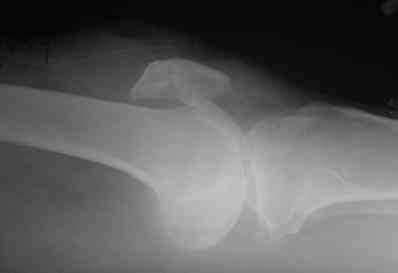

прилагаю снимки надколенника.

На снимке восстановление разрыва quad связки, только швы завязывается внизу надколенника, и примерный рисунок техники.